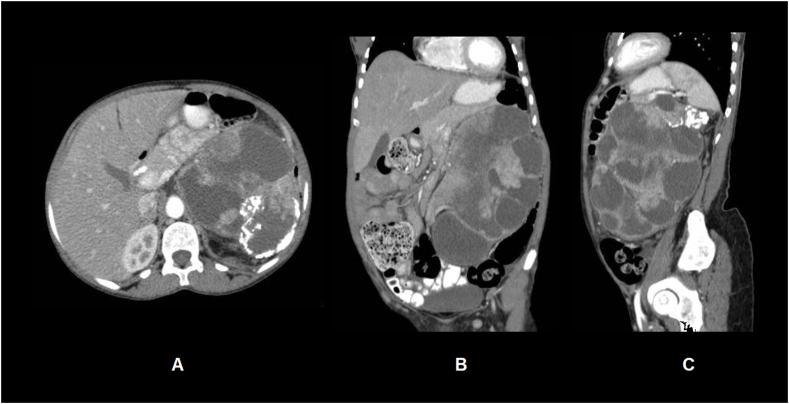

TFE3-rearranged renal cell carcinoma (RCC) is a rare but well characterised histological subtype of RCC with an aggressive clinical course and propensity for late metastases. Osseous metaplasia is an uncommon but well documented finding in clear cell, papillary and chromophobe RCC. We present the first case of a -rearranged RCC to be found harbouring metaplastic bone in a 47-year-old woman who presented with a slowly enlarging left flank mass over a 10 year period. This case report adds to the clinicopathological description of -rearranged RCC and suggests that larger studies are required to fully elucidate the prognosis of these tumours.

TFE3 重排肾细胞癌(RCC)是一种罕见但特征明确的肾细胞癌组织学亚型,临床病程侵袭性强,易发生晚期转移。骨化生在透明细胞型、乳头状和嫌色细胞型肾细胞癌中并不常见,但已有充分记录。我们报告首例TFE3重排肾细胞癌病例,该病例发生于一名47岁女性,她在10年期间出现左侧腰部缓慢增大的肿块,且伴有化生骨。本病例报告补充了TFE3重排肾细胞癌的临床病理描述,并表明需要进行更大规模的研究以充分阐明这些肿瘤的预后。